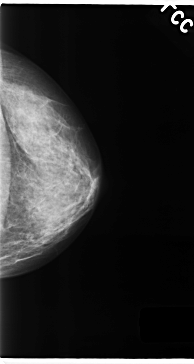

C_0154_1.LEFT_MLO

C_0154_1.LEFT_CC

LEFT_CC LINES 4728 PIXELS_PER_LINE 2512 BITS_PER_PIXEL 12 RESOLUTION 50 NON_OVERLAY

LEFT_MLO LINES 4712 PIXELS_PER_LINE 2632 BITS_PER_PIXEL 12 RESOLUTION 50 NON_OVERLAY